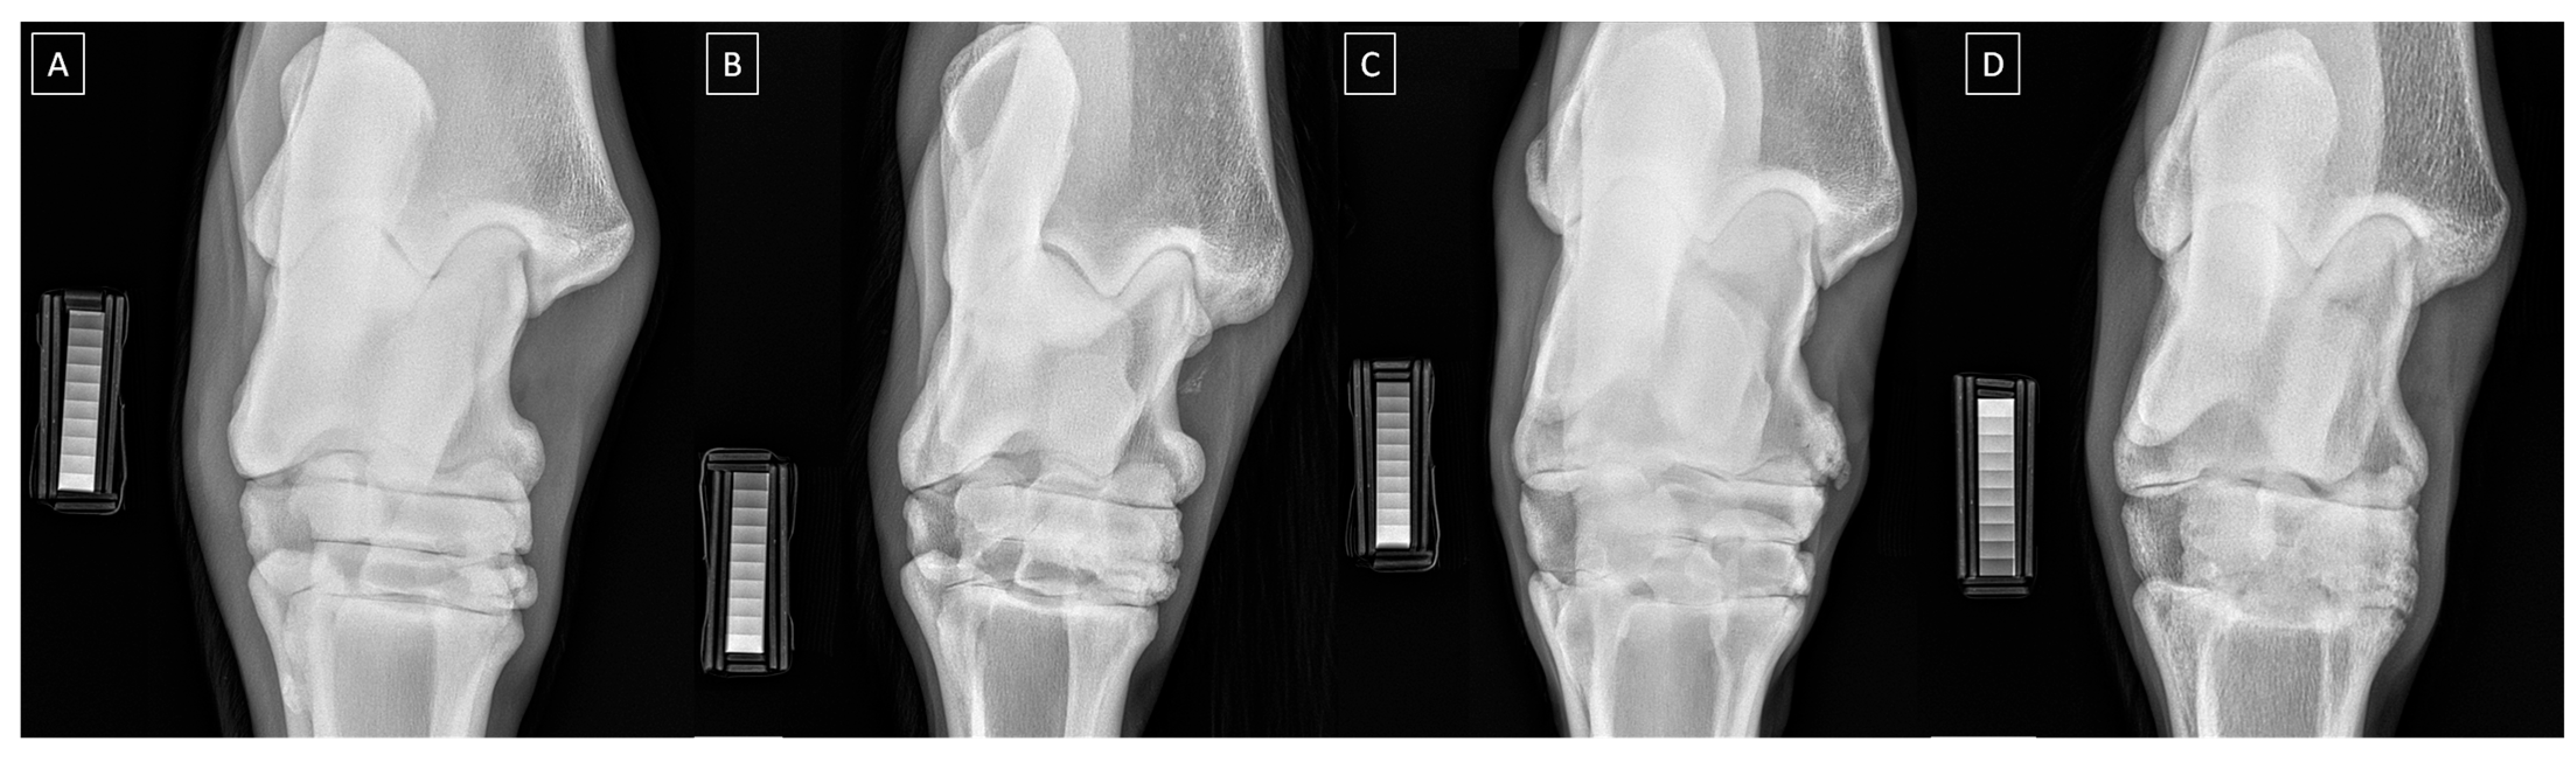

| Grade | Severity | Radiographic Signs |

|---|---|---|

| 0 | Normal | Normal width and shape of the joint space; smooth cortical bone surface; normal subchondral bone pattern; no periosteal proliferation; no intra-articular mineralization |

| 1 | Mild | Narrow and irregular joint space with osteophytes; irregular cortical bone surface with well-defined protuberance; smooth subchondral bone pattern; flat periosteal proliferation; mild intra-articular mineralization |

| 2 | Moderate | Narrow and irregular joint space with multiple osteophytes, enthesiophytes, and marked asymmetry; irregular cortical bone surface with well-defined bone proliferation; subchondral bone cyst; flat periosteal proliferation; moderate intra-articular mineralization |

| 3 | Severe | Completely narrow joint space with large osteophytes and enthesiophytes; severe deformation of cortical bone surface; subchondral bone sclerosis; flat or intense periosteal proliferation; severe intra-articular mineralization |